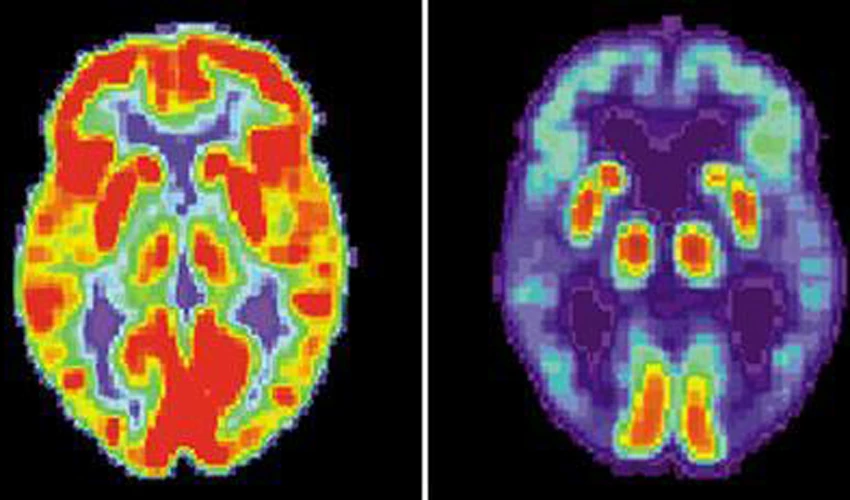

While the lesions of those who stopped smoking were not located in one specific region of the brain, they mapped them to a number of areas -- what they called the "addiction remission network".

They found that a lesion that would cause someone to give up an addiction would probably affect parts of the brain like the dorsal cingulate, lateral prefrontal cortex and insula -- but not the medial prefrontal cortex.